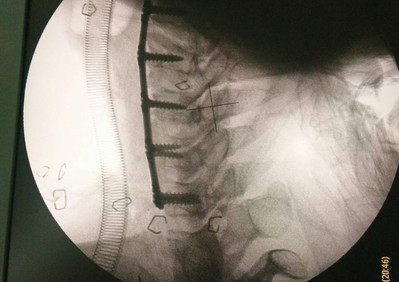

Anterior Cervical Plate System

El sistema de placas cervicales Prodorth está diseñado para satisfacer las expectativas clínicas de la cirugía cervical anterior y ofrece una amplia gama de tamaños de placas y tornillos.

- Placas predobladas de bajo perfil (2,0 mm).

- El sistema de placa cervical de Prodorth consta de placas cervicales, casquillos de cierre, tornillos óseos y los instrumentos necesarios para implantar este sistema específico. Todos los componentes del implante están hechos de una aleación de titanio Ti6Al4V-ELI (Grado 23) (ASTM F136 / ISO 5832-3).